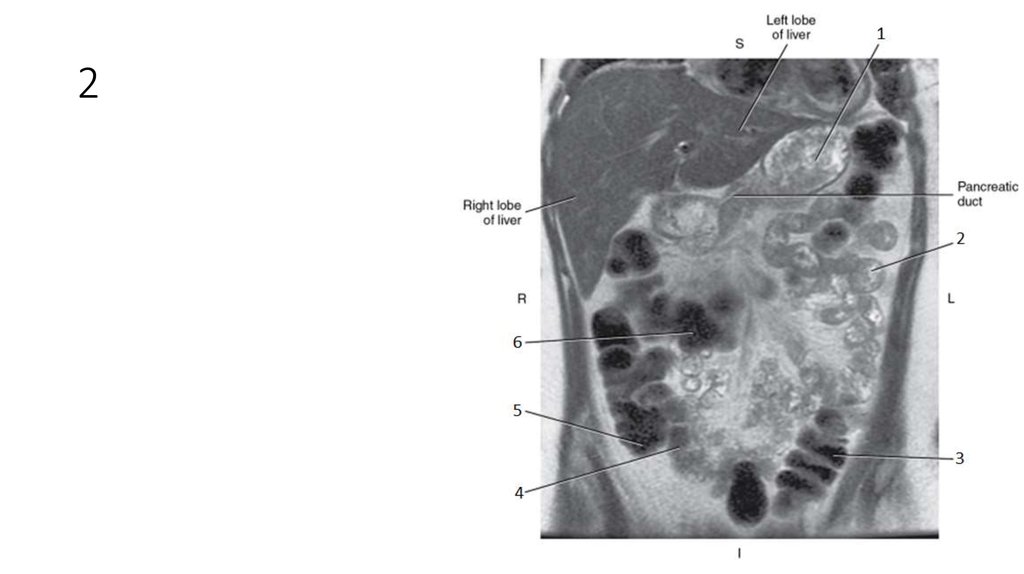

32. 1

33. 1

• Intrahepatic Ducts

34. 2

35. 2

• Pancreatic Duct

36. 3

37. 3

• Common Bile Duct

38. 4

39. 4

• Cystic Duct

40. 5

41. 5

• Common Hepatic Duct

42. 6

43. 6

• Gallbladder